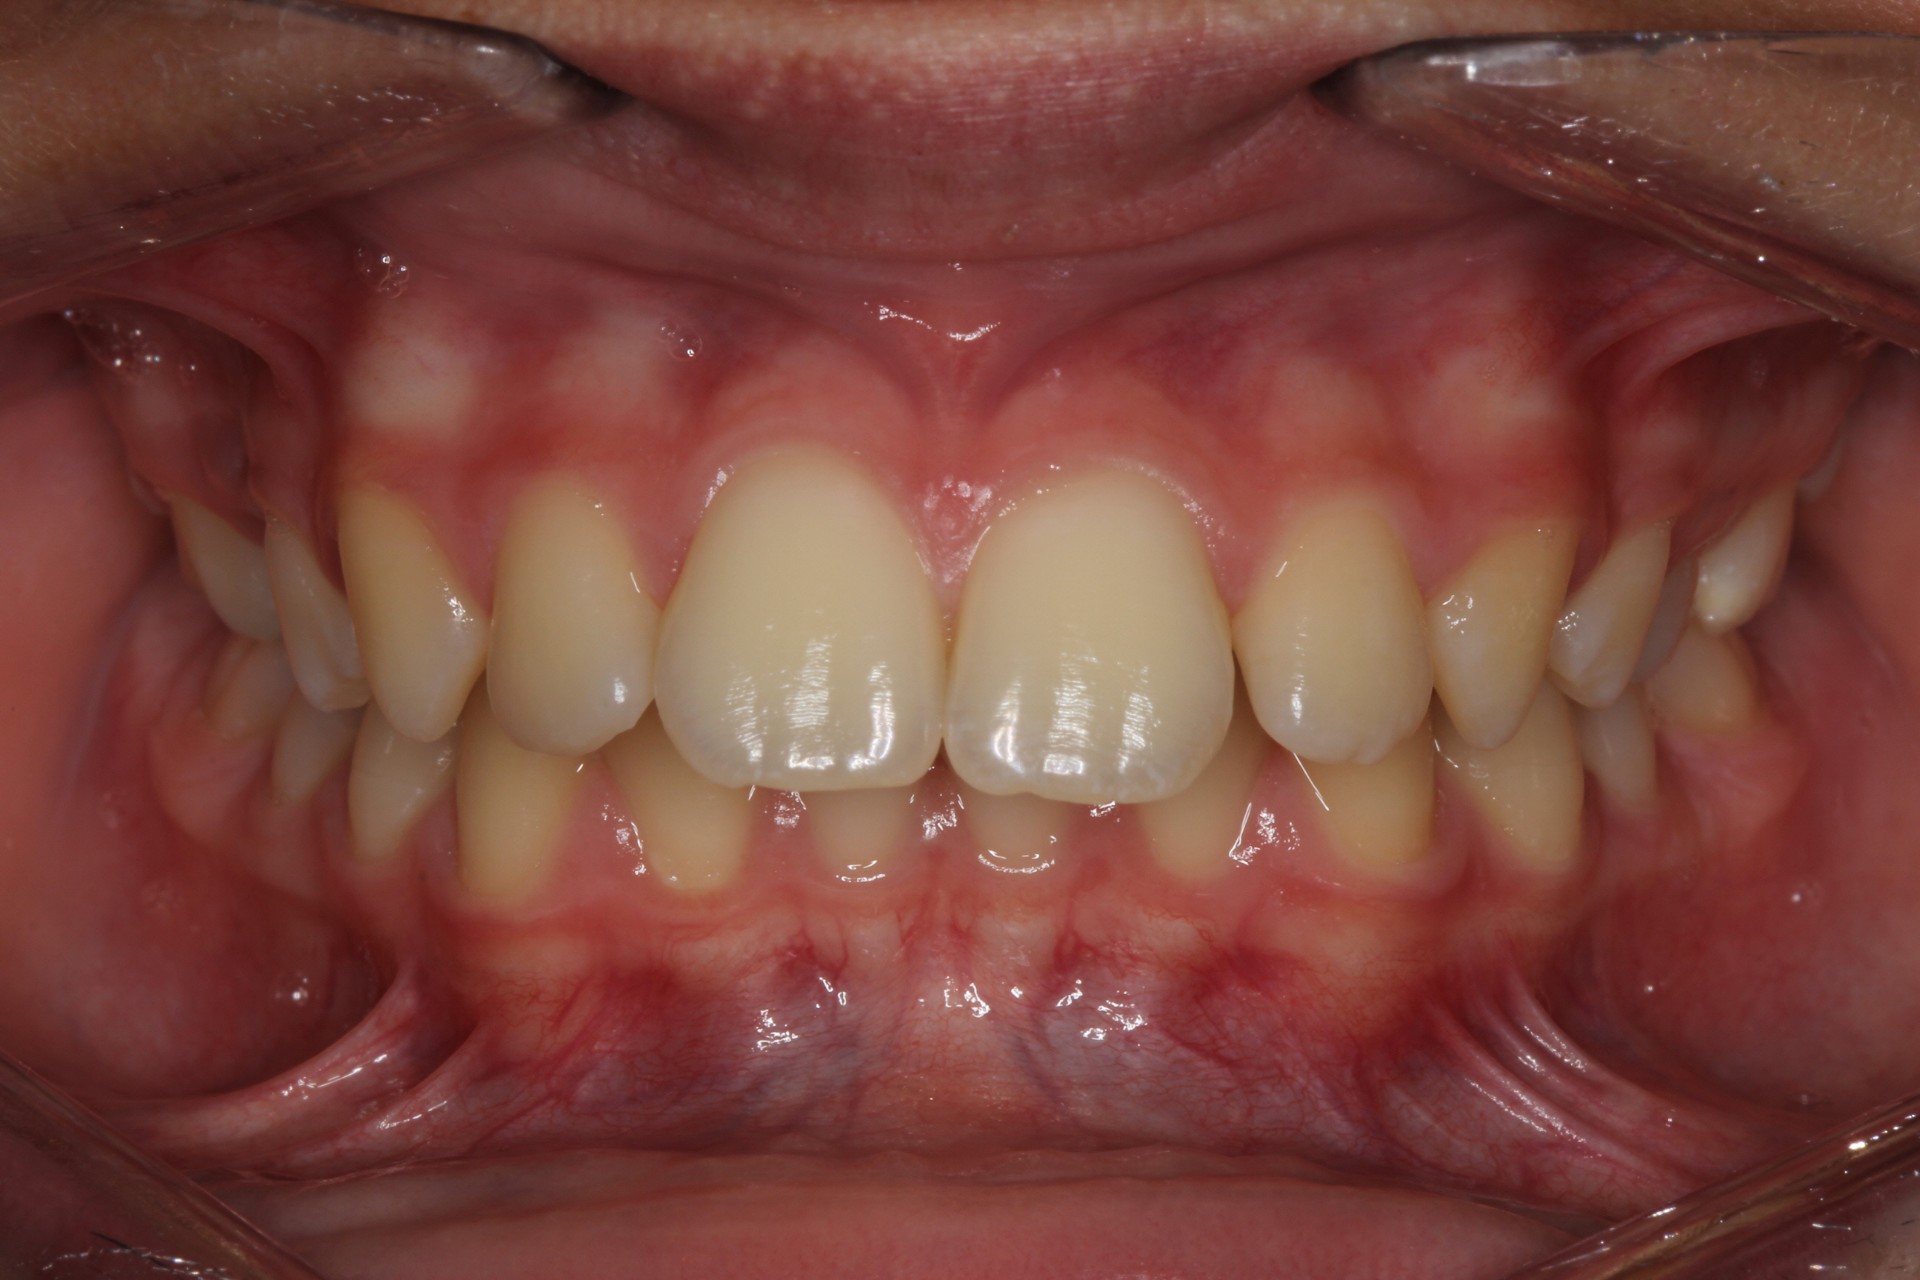

Protruding front teeth – Child case